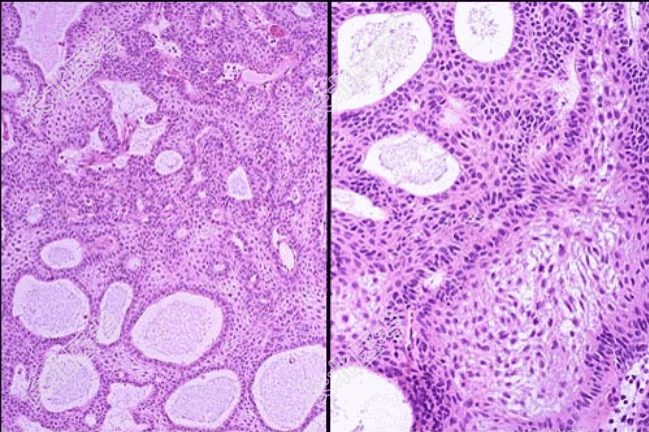

- [材料题] 患者男性,18岁,因颅内肿瘤手术,术中见肿瘤位于蝶鞍上部,球形,有包膜,直径3cm。术后巨检肿块囊实性,囊内充满淡黄色液体,实性区灰白色,质硬,镜检如图,临床诊断为颅咽管瘤。

- 简答题1、该疾病病理特点表现为?